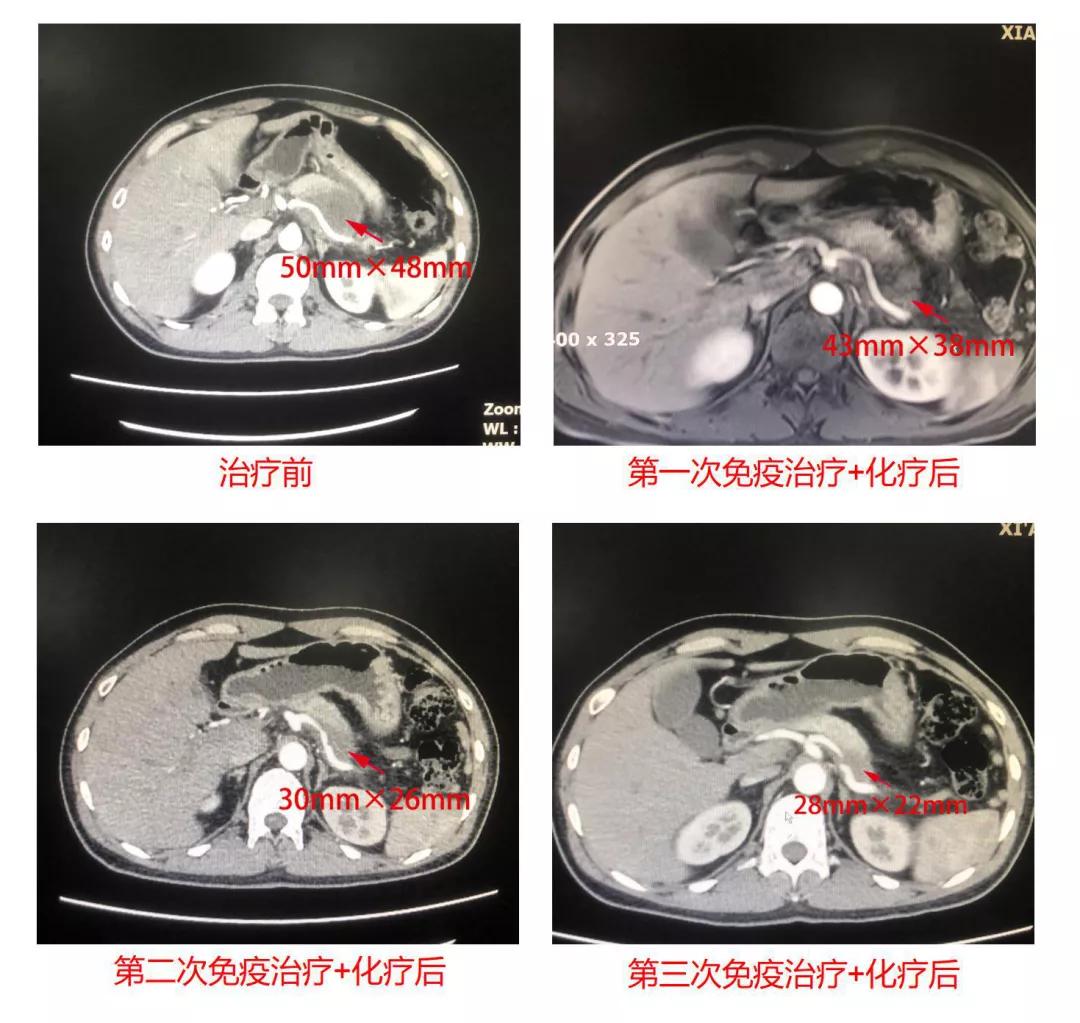

在肝胆外科的积极安排下,张先生先后于2020年12月6日、2021年1月5日 及 1月29进行了免疫治疗+化疗,在肝胆外科医护人员全力以赴、张先生乐观配合下,三次治疗均顺利完成。随后的影像学检查也充分证实效果显著,胰腺病灶明显缩小,由治疗前的50mm×48mm缩小至28mmx22mm。